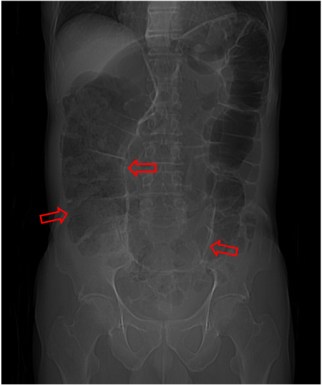

SIGNO DE LAS LÍNEAS CONVERGENTES

Es un signo de vólvulo de sigma que se ve al tiempo que el Signo del grano de café, pero no referido al luminograma del sigma dilatado sino a las paredes sigmoideas. Se trata de tres líneas que delimitan la pared del sigma (flechas), dos laterales y una central, más gruesa, formada por la aposición de las paredes de las dos partes del sigma, la que asciende y la que desciende. Las tres líneas convergen en la pelvis en la zona de la volvulación.

La imagen ha sido cedida por Federico Cáceres, de su blog Radiodiagnosticando:

http://radiodiagnosticando.com/2014/07/11/caso-volvulo-de-sigma/.

Este signo se ha denominado también Signo de Frimann-Dahl.

SIGNO DEL PASO AL NORTE

La misma imagen del signo anterior nos permite ilustrar este otro. En el vólvulo de sigma, la parte más alta de éste se sitúa por encima del colon transverso (marcado en amarillo en la imagen).